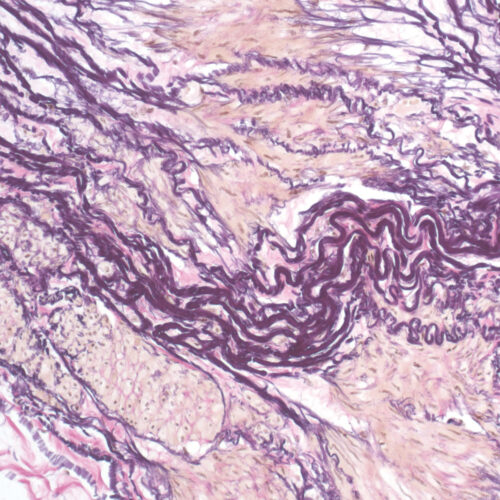

Elastica-Van Gieson kit

Four-reagent kit for staining elastic fibers and differentiation between elastic tissue, collagen and other types of connective tissue. The rapid method enables a satisfactory result with shorter section staining time.